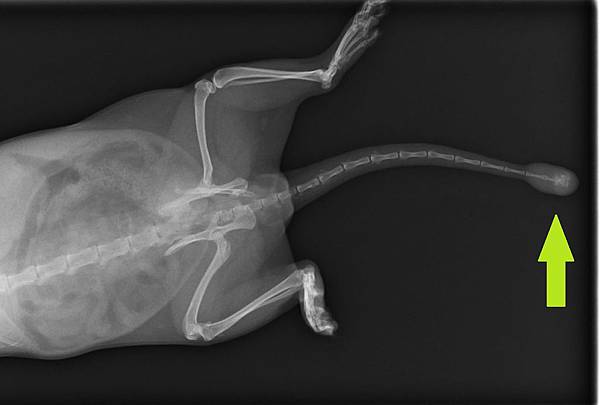

本病例為3.5歲公貂,已絕育,發現已超過半年,發生時間不確定,臨床檢查及X光檢查後初步判定應為尾脊瘤,建議切除

就診時X光片,可見尾椎椎骨已被侵蝕出現再骨化情形